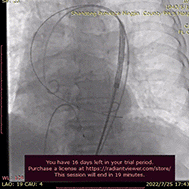

手术过程概览

在Ecmo辅助下,行主动脉根部造影,猪尾确定选择最佳释放体位,观察瓣叶活动,确认是否合并反流,选择合适体位跨瓣。

主动脉根部根部造影

术者团队用25mm球囊预扩,结合瓣环及球囊预扩情况,预装AV29型号瓣膜。患者横位心,在抓捕器辅助下输送器过弓。

球囊预扩

造影评估

术者结合DSA影像,多角度观察瓣膜情况,在瓣膜释放至工作位造影。

初始定位释放

工作位

无明显返流,瓣膜形态佳,工作稳定。

工作位评估

完全释放

术后超声评估

术前超声:主动脉瓣最大流速6.5m/s,平均压差48mmHg

术后超声:主动脉瓣最大流速2.0m/s, 平均压差16mmHg